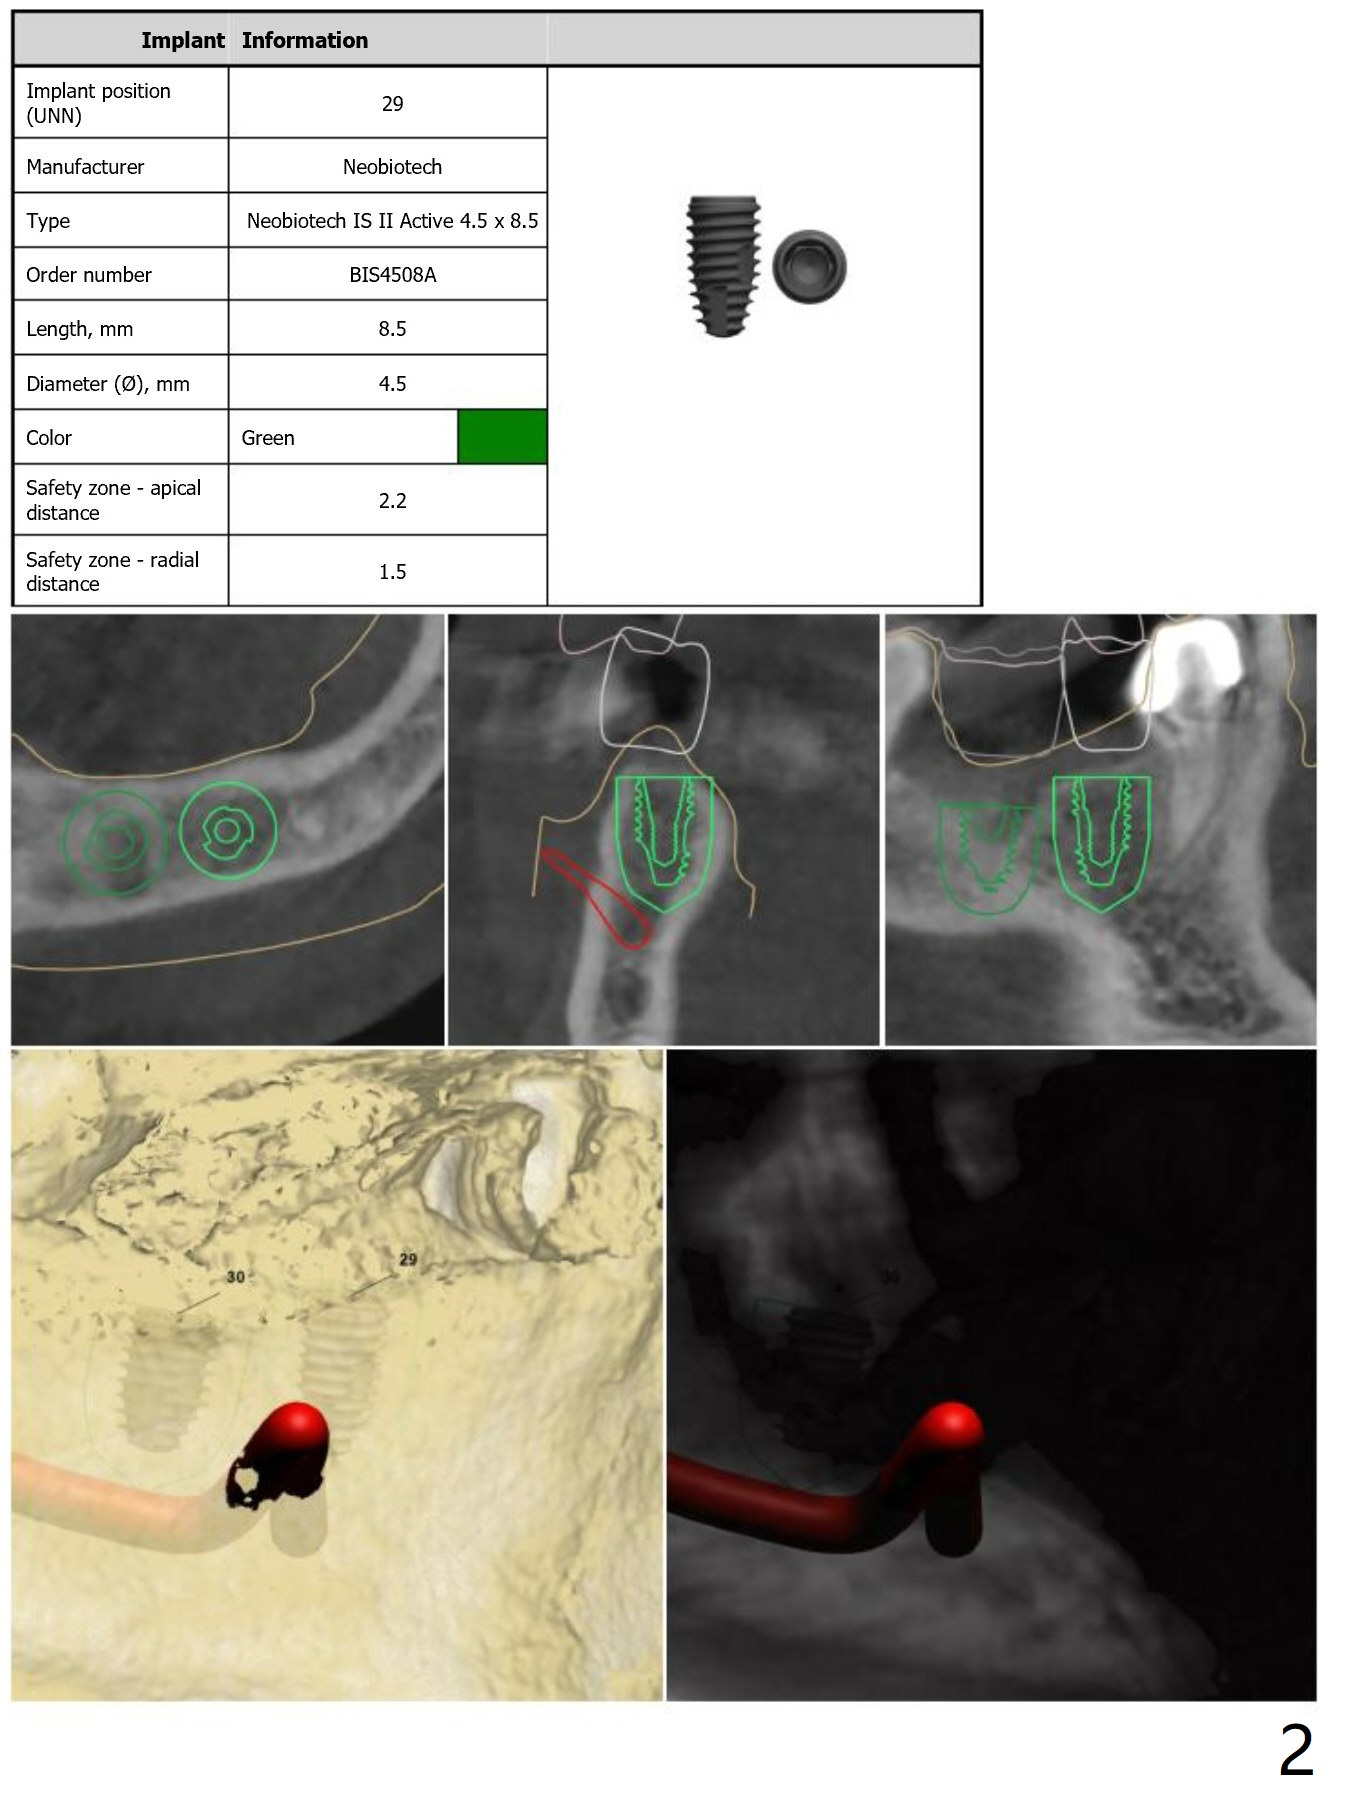

Return to Lower Arch  Molar Premolar  Immediate Implant, Trajectory